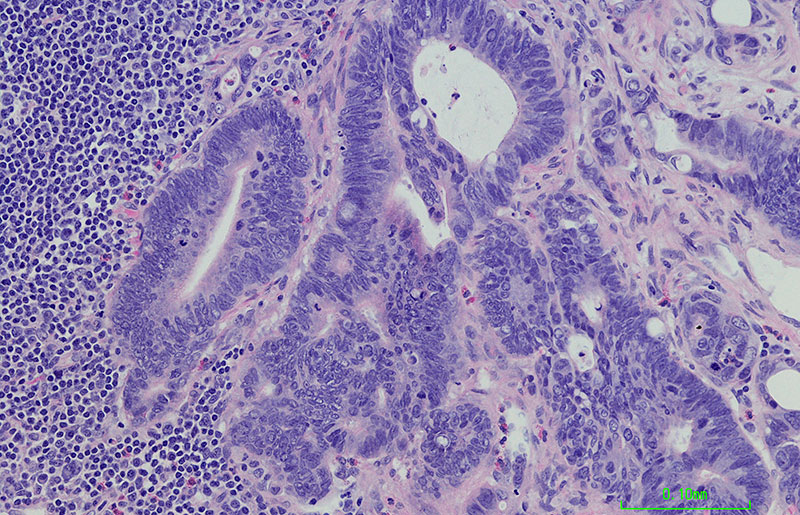

blood cancer shown under microscope

Moffitt's CARDIO-CATCH Clinic for Clonal Hematopoiesis